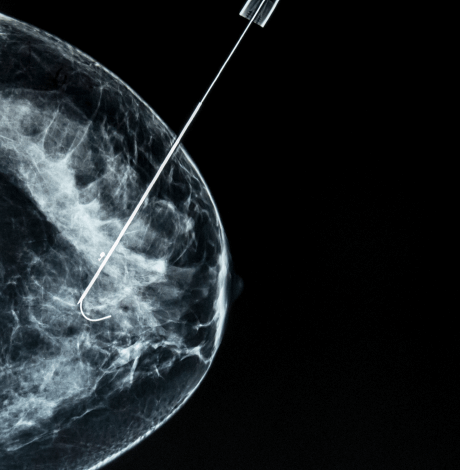

A mastectomy is a high-risk surgical procedure commonly referred to as breast removal surgery and generally aims for cancerous tissue removal either partially or completely from one or both breasts.